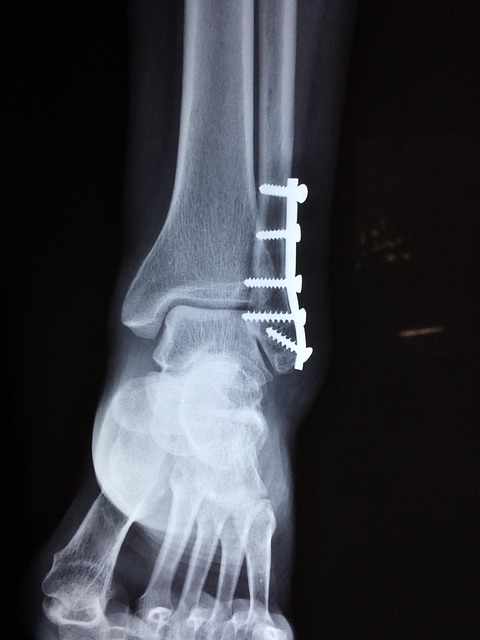

만약 발목 접질림 증상이 심해서 병원 진료를 받게 되면, 의사 선생님은 먼저 X-ray, 초음파, MRI 같은 검사를 통해 인대가 얼마나 다쳤는지, 혹시 뼈가 부러진 건 아닌지 꼼꼼하게 확인해 줄 거예요.